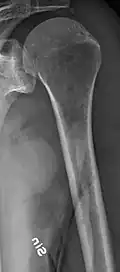

Multiple myeloma in the upper arm -

Humerus with multiple myeloma lesions -

Same humerus before, with just subtle lesions